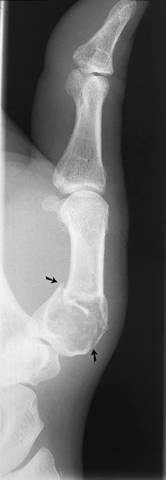

Kuva 1.

Murtuma I metakarpaaliluun diafyysin tyvessä.

Sivukuva näyttää, että kulmamuodostus on melkoinen. Murtumalinja kulkee enkondrooman lävitse ja se on siis patologinen.